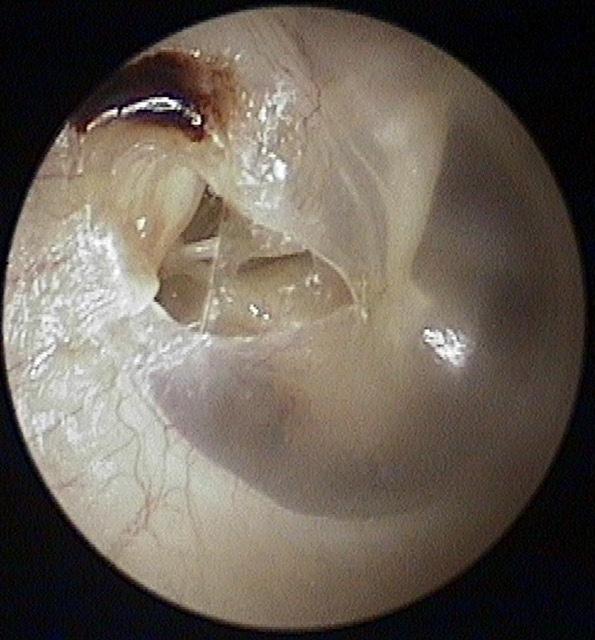

Perforation